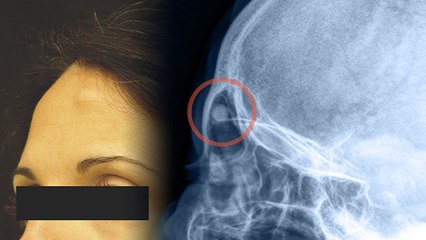

Liver Damage Signs In Eyes: आंखों में दिखने वाले ये संकेत लिवर की गंभीर समस्या की ओर इशारा कर सकते हैं। आंखों का पीला होना, खुजली, लालिमा या काले घेरे इन लक्षणों को नज़रअंदाज़ न करें। समय पर जांच और सही लाइफस्टाइल से लिवर को बचाया जा सकता है। br #LiverDamageSignsInEyes br #YellowEyesLiverProblems br #liverdamageearlysigns br #liverdamagesigns br #signsofliverdamageineyes br #liverdamagekeankhonmeinkyalakshanhotehain br #liverdamagekekyalaskhanhai br #livereyesproblemkekyalakshanhai br #liverdamagehonekelakshan br #लिवरखराबहोनेकेलक्षणbr br ~ED.